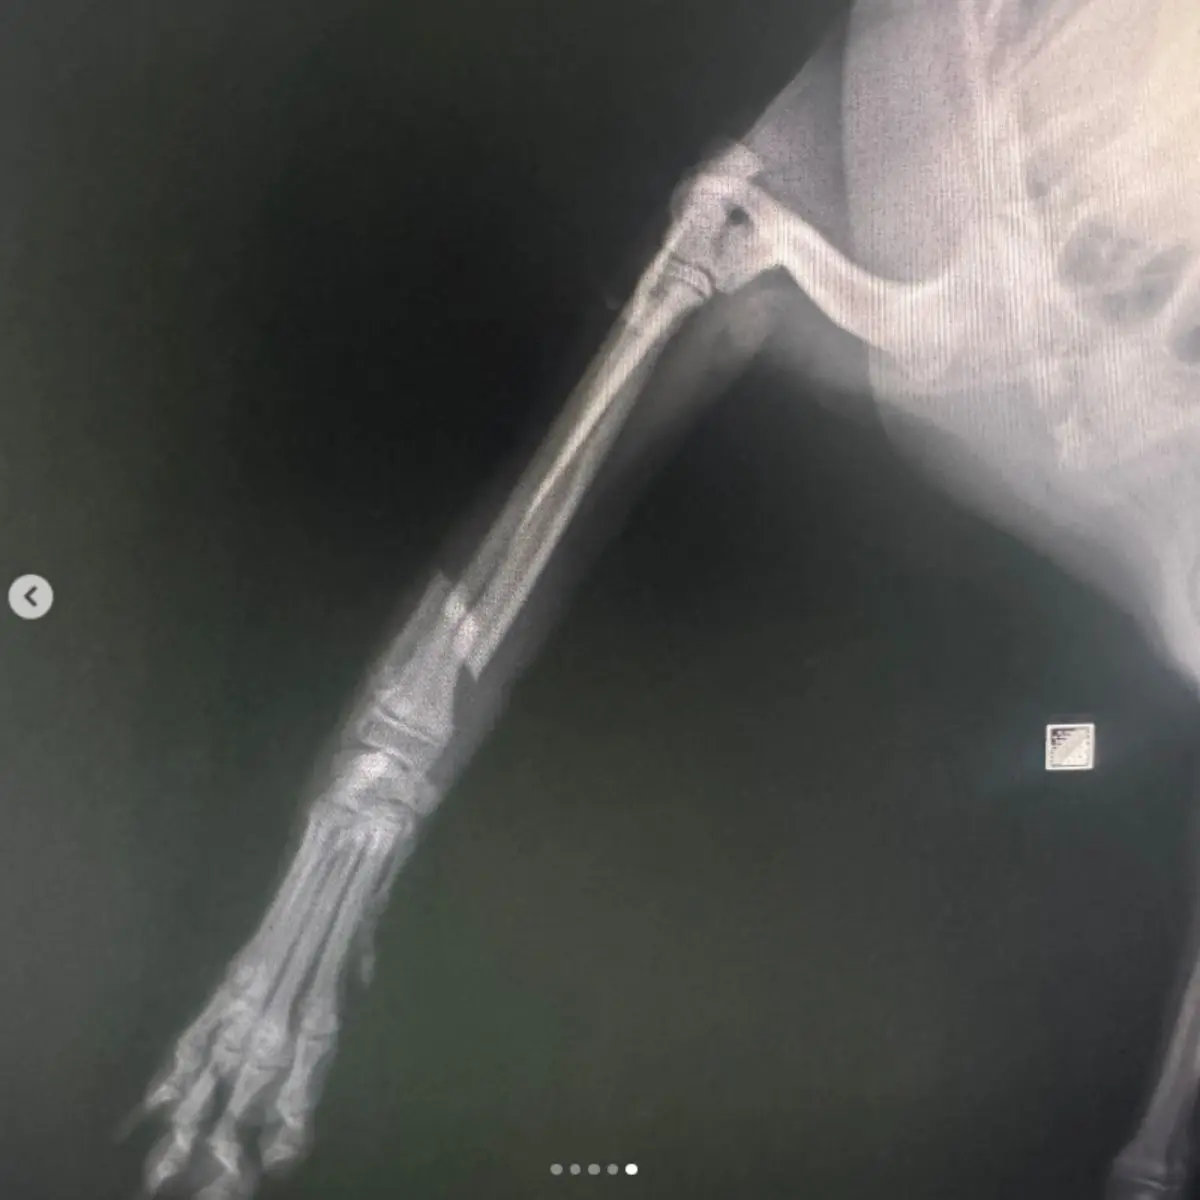

Vida ile Sabitleme ve Düzeltme: Kemik kırıklarını stabilize etmek ve doğru pozisyonda kaynamasını sağlamak için uygulanır.

Pin ile Sabitleme ve Düzeltme: İnce metal çubuklar kullanılarak kırıklar ve eklem deformiteleri düzeltilir.

Eksternal Fiksatör ile Sabitleme ve Düzeltme: Kırık veya çıkıkları dışardan sabitleyen cihazlarla tedavi edilir.

Plak ile Sabitleme ve Düzeltme: Kemiklerin doğru şekilde birleşmesi için cerrahi olarak plak ve vida sistemi uygulanır.